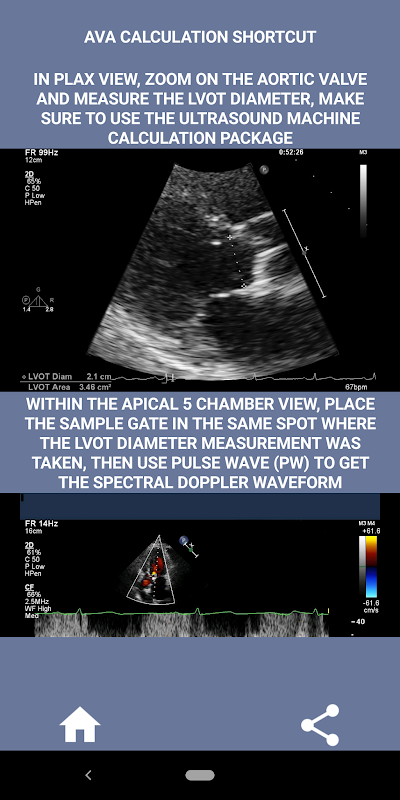

Pada pendapat saya, sekiranya seseorang yang ditemubual dapat menunjukkan keahlian ini, seseorang itu mempunyai kelebihan besar berbanding pemohon lain yang lemah dalam bidang ini (itu adalah logik kerana biasanya terdapat banyak kes stenosis aorta). Sekiranya anda melamar posisi sonographer jantung, seseorang yang hanya perlu menyegarkan kemahirannya, atau pelajar echo, maka aplikasi ini direka oleh anda oleh sonographer jantung yang sedang berlatih. Ringkas dan pendek, tepat dengan banyak video ilustrasi yang menunjukkan dengan tepat di mana untuk mengukur (mis. Diameter LVOT) dan cara mengukur mengikut garis panduan ASE / ICAEL yang diterbitkan.